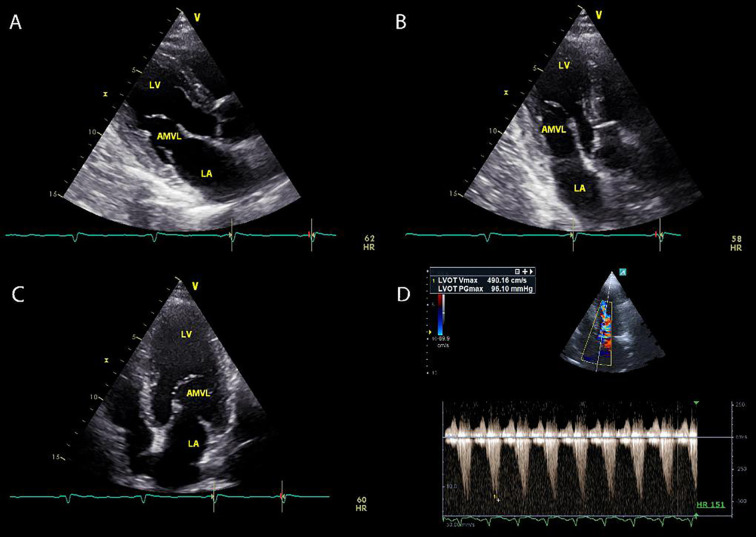

An Unusual Etiology of Presyncopal Episodes: Dynamic Left Ventricular Outflow Tract Obstruction Secondary to an Elongated Anterior Mitral Valve Leaflet.